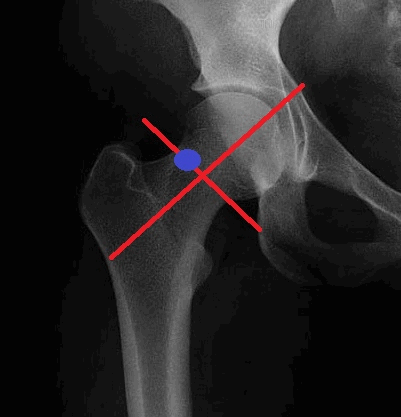

Маркеры для введения контраста: важно не затрагивать сухожилие пояснично-крестцовой мышцы и бедренную артерию.

Под контролем флюороскопа рисуется виртуальная линия разделяющая головку и шейку бедра и другая линия перпендикулярно заданной. Несколько выше точки их пересечения маркируется отметка.

Контрастирование: теперь обработайте помеченную область раствором бетадина и обезбольте кожу и подлежащие ткани 1% раствором лидокаина.

Для проведения МР артрограмм при контрастировании применяют иглы A 22 G 3½. Теперь поместите кончик иглы на отметку и при помощи флюороскопа проконтролируйте введение иглы в полость сустава. Затем введите от 10 до 15мл разведенного магневиста в следующей пропорции:

5мл физиологического раствора, 2мл омнипака, 2мл 1% р-ра лидокаина и 0,1 мл магневиста.